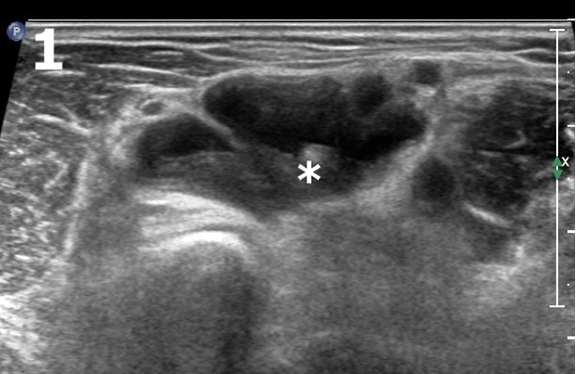

A 63-year-old Chinese female with seropositive rheumatoid arthritis (RA) presented with three days history of painful left forearm swelling and fever after switching to anti-tumor necrosis factor therapy for two months. There was no recent history of injury reported. Physical examination showed a swelling at the antecubital area which was tender on palpitation. X-ray of elbow and forearm were normal. Blood test showed elevated C-reactive protein 108 ng/L ( <5 ng/L) and ESR 119 mm/hr (3–28 mm/hour). Initial diagnoses were cellulitis, inflammatory lesion or soft tissue mass. Ultrasonography demonstrated a poorly compressible, well-circumscribed anechoic collection with both solid and fluid component surrounding the distal biceps tendon (Figure 1), over the anterior aspect of cubital fossa (Figure 2) with power Doppler signals. The elbow joint was normal without synovitis or effusion. Sonographic features suggestive of bicipitoradial bursitis need to rule out septic bursitis. Ultrasound-guided aspiration and decompression of the lesion was performed, yielded slight blood-stained fluid, both bacterial and mycobacterium culture was negative. Her fever responded to course of antibiotics and anti-inflammatory drugs. The swelling completely resolved after one week.

Figure 1: Bicipitoradial bursitis in a patient with rheumatoid arthritis. Ultrasound scan of antecubital area in transverse view showed an anechoic lesion (*) surrounding the distal biceps tendon suggestive of bicipitoradial bursitis.